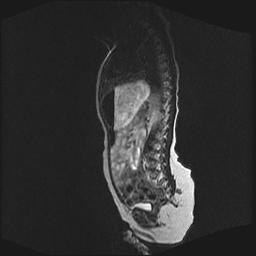

四个月的女婴,ct示脊膜膨出.

脊柱裂、脊膜膨出,请结合临床除外皮毛窦。

脂肪脊髓脊膜膨出

脊柱裂、脊膜膨出